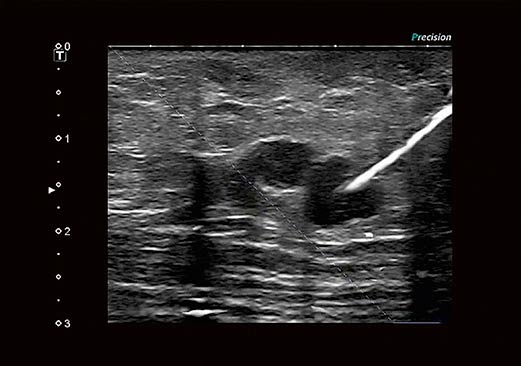

Технология улучшения визуализации биопсийной иглы BEAM, разработанная корпорацией Canon Medical Systems, в режиме реального времени обеспечивает четкое отображение кончиков игл на эхограмме.

Технология BEAM обеспечивает четкое отображение пункционных игл без необходимости выбирать оптимальный угол сканирования.